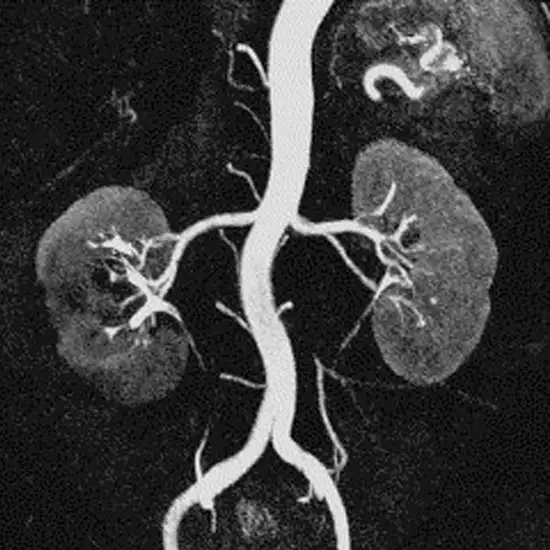

Magnetic resonance angiography (MRA) employs MRI and IV contrast dye to see blood vessels. An MRA checks the heart, soft tissues, and blood flow. The contrast dye makes blood arteries opaque on MRI images, allowing doctors to assess them.

For diagnosing renal artery stenosis. Renal artery stenosis is when one or both kidney arteries get smaller. Your kidneys get blood from these blood vessels. They also help keep the body's blood pressure in check.